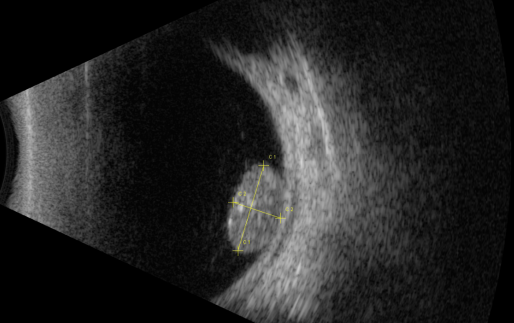

視網(wǎng)膜母細(xì)胞瘤的分類和治療

視網(wǎng)膜母細(xì)胞瘤是嬰幼兒常見的眼內(nèi)惡性腫瘤,可危害患者的視力、眼球和生命。其惡性程度高,多發(fā)于兒童,尤其是3歲以下的兒童,常表現(xiàn)為白瞳癥,可侵及單眼或雙眼。

視網(wǎng)膜母細(xì)胞瘤分類

根據(jù)腫瘤的表現(xiàn)和發(fā)展過程可分為眼內(nèi)期、青光眼期、眼外期和全身轉(zhuǎn)移期。

開始在眼內(nèi)生長時(shí)外眼正常,因患兒年齡小,不能自述有無視力障礙,因此本病早期一般不易被家長發(fā)現(xiàn)。當(dāng)腫瘤增殖突入玻璃體或接近晶體時(shí),瞳孔區(qū)出現(xiàn)黃白色反光,如貓眼樣(“黑貓眼”),此時(shí)常因視力障礙而瞳孔散大、白瞳癥或斜視被家長發(fā)現(xiàn)。